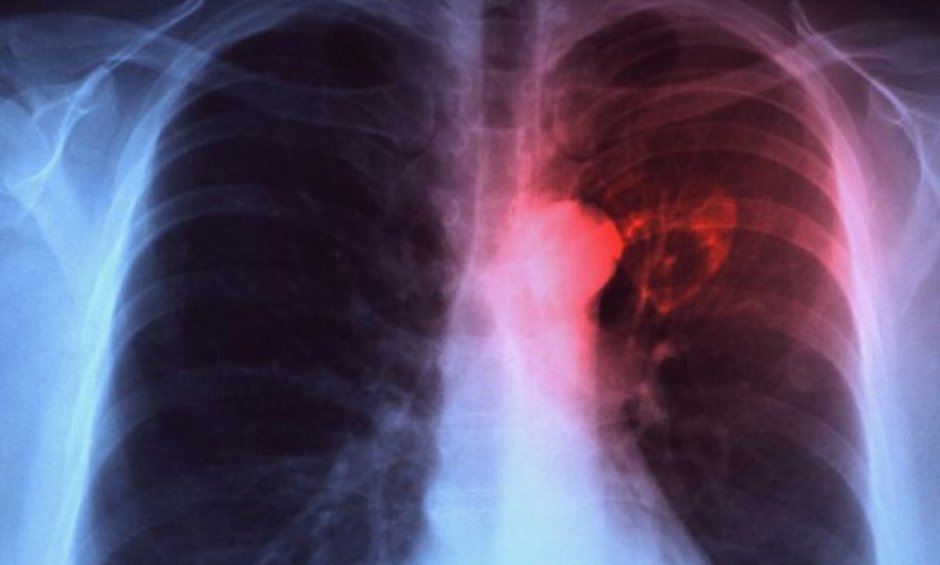

Η παγκόσμια μέρα της φυματίωσης πραγματοποιείται κάθε χρόνο στις 24 Μαρτίου, σηματοδοτώντας τη μέρα του 1822 όταν ο Δρ. Robert Koch ανακοίνωσε την ανακάλυψη του βακτηρίου που προκαλεί τη φυματίωση.

Σύμφωνα με τα τελευταία δημοσιευμένα στοιχεία του Παγκόσμιου Οργανισμού Υγείας (WHO) και του Ευρωπαϊκού Κέντρου Ελέγχου και Πρόληψης Νοσημάτων (ECDC), το 2015 εκτιμάται ότι σημειώθηκαν παγκοσμίως 10.400.000 νέες περιπτώσεις φυματίωσης, από τις οποίες οι 323.000 στην Ευρώπη. Παρά το γεγονός της ύπαρξης αποτελεσματικής θεραπείας, το 2015 η φυματίωση ήταν υπεύθυνη για το θάνατο 1.8 εκατομμυρίου ανθρώπων, 400.000 από τους οποίους ήταν ασθενείς με HIV λοίμωξη, αποτελώντας μία από τις 10 συχνότερες αιτίες θανάτου παγκοσμίως και το συχνότερο αίτιο θανάτου από λοιμώδες νόσημα, προκαλώντας περισσότερους θανάτους από την HIV λοίμωξη και την ελονοσία. Πάνω από το 95% των θανάτων από φυματίωση σημειώνονται σε χώρες χαμηλού και μέτριου εισοδήματος, γεγονός που καταδεικνύει την ανάγκη αντιμετώπισης των ανισοτήτων όσον αφορά την πρόσβαση στη διάγνωση και τη θεραπεία της νόσου. Η φυματίωση ευθύνεται για το 35% των θανάτων των ασθενών με HIV λοίμωξη, αποτελώντας κύριο αίτιο θανάτου σε αυτή την ομάδα πληθυσμού.

Στην Ελλάδα, με βάση τα επιδημιολογικά δεδομένα του ΚΕ.ΕΛ.Π.ΝΟ, για το χρονικό διάστημα 2004-2015, δηλώνονται ετησίως κατά μέσο όρο 600 περιπτώσεις φυματίωσης, με τη μέση επίπτωση της νόσου να υπολογίζεται στις 4,6 περιπτώσεις ανά 100.00 πληθυσμού. Το 2011 δηλώθηκαν 476 κρούσματα. Σε γενικές γραμμές, κατά το προαναφερθέν διάστημα παρατηρήθηκε μικρή πτωτική τάση του ετήσιου αριθμού δηλούμενων περιπτώσεων. Επισημαίνεται πάντως ότι εξακολουθεί να διαπιστώνεται σημαντική υποδήλωση του νοσήματος, με αποτέλεσμα να μην αποτυπώνεται με σαφήνεια η επιδημιολογική εικόνα της φυματίωσης στη χώρα. Από τα διαθέσιμα στοιχεία, κατά την τελευταία πενταετία έχει παρατηρηθεί αύξηση του αριθμού των περιπτώσεων φυματίωσης σε ασθενείς που ανήκουν σε ευάλωτες κοινωνικές ομάδες (ασθενείς με HIV λοίμωξη, κρατούμενους, χρήστες ουσιών). Τα ποσοστά ασθενών με ανθεκτικές μορφές φυματίωσης (MDR/XDR-TB) έχουν παραμείνει σταθερά και είναι υψηλότερα μεταξύ ασθενών αλλοδαπής εθνικότητας.